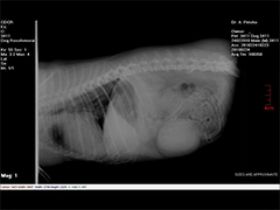

היפוך קיבה אצל כלב